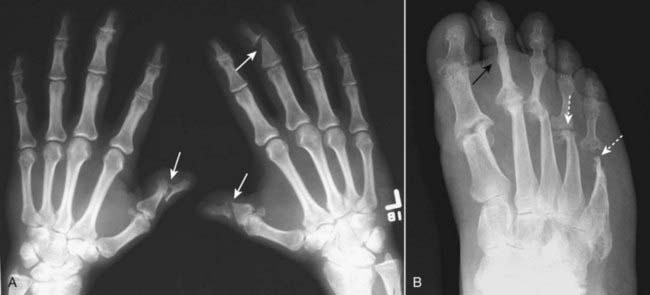

Figure 23-12 Calcium pyrophosphate deposition disease (CPPD).

CPPD arthropathy produces changes similar to osteoarthritis but differs from it in that CPPD affects joints not usually affected by primary osteoarthritis. A, Hook-shaped bony excrescences along the 2nd and 3rd metacarpal heads are a common finding in CPPD (solid white arrows). The radiocarpal joint is narrowed (solid black arrow). B, In the wrist, characteristic findings include calcification of the triangular fibrocartilage (solid white arrow), separation of the scaphoid (S) and the lunate (L) (scapholunate dissociation) and collapse of the capitate (C) toward the radius (solid black arrow) called scapholunate advanced collapse (SLAC).

Figure 23-13 Rheumatoid arthritis, hand (A) and wrist (B).

A, In the hand, the erosions of RA tend to involve the proximal joints: the carpal-metacarpal joints, metacarpal-phalangeal (solid white arrows), and proximal interphalangeal joints. Late findings in the hands include deformities such as ulnar deviation of the fingers at the MCP joints, subluxation of the MCP joints, and ligamentous laxity leading to deformities of the fingers, which are also present in this hand. B, In the wrist, erosions of the carpals (dotted white arrow), ulnar styloid (solid white arrow), and narrowing of the radiocarpal joint space (solid black arrow) are commonly seen.